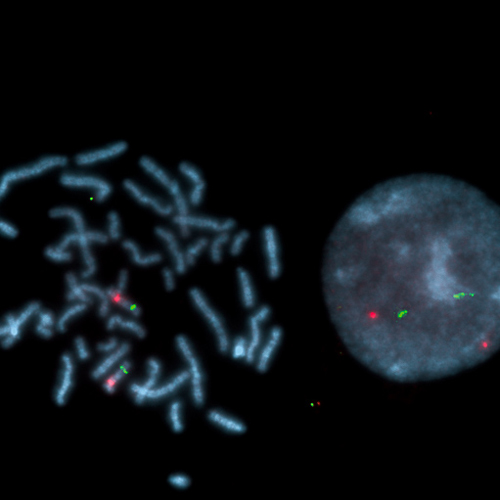

Angelman UBE3A (15q11) / PML (15q24) probe hybridized to a normal interphase/metaphase (2R2G).

Angelman syndrome (AS) is characterized by severe developmental delay or mental retardation, severe speech impairment, gait ataxia and/or tremulousness of the limbs, and an unique behavior with an inappropriate happy demeanor that includes frequent laughing, smiling, and excitability. In addition, microcephaly and seizures are common. AS is caused by absence of a maternal contribution to the imprinted region on chromosome 15q11-q13 including the UBE3A gene. The AS UBE3A region probe is optimized to detect copy numbers of the UBE3A gene region at 15q11. The PML (promyelocytic leukemia) gene specific FISH probe at 15q24 is included as control probe.